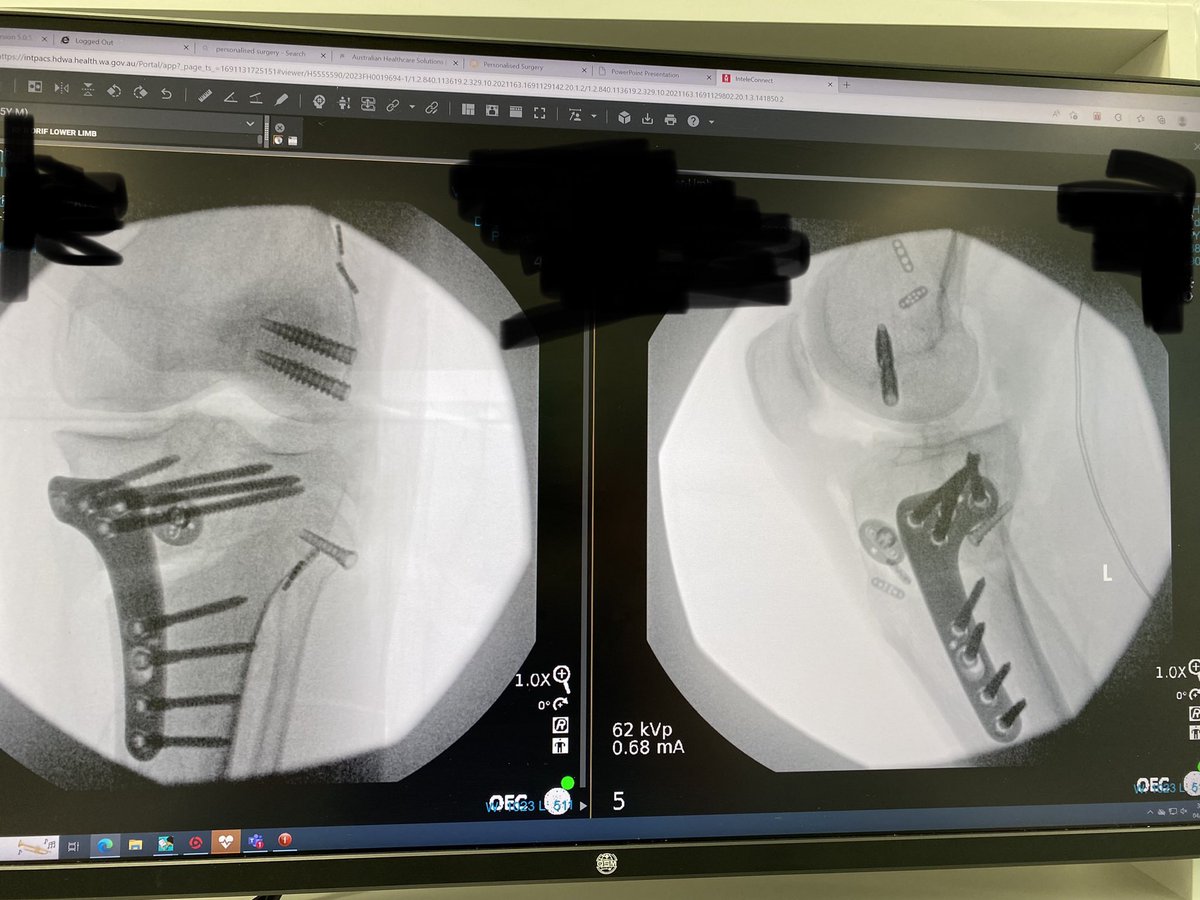

Incredible 1st 6 weeks of the Sports Surgery Fellowship in Perth. ACL's, PCL's, root repairs, multi-ligs, OATS, OCA, revision ACLs, Hip scopes. Not to mention the lifestyle. Highly recommend to those interested in soft tissue/joint preservation @BASKtrainees @58society @bota_uk